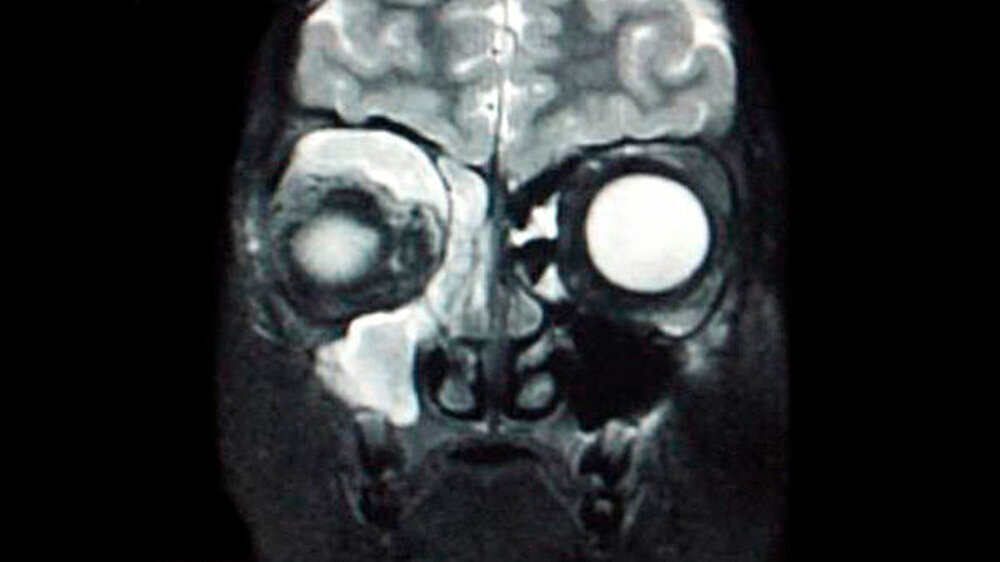

Aufgrund dieser Befunde und der klinischen Untersuchung wurde zur weiteren Abklärung eine Magnetresonanztomografie des Mittelgesichts veranlasst. Dabei sah man eine deutliche Protrusio bulbi rechts mit hierdurch gestrecktem Verlauf des N. opticus. Des Weiteren konnte man eine Schleimhautschwellung mit kompletter Sekretausfüllung des Sinus maxillaris rechts ausmachen. Flüssigkeitsverhalte zeigten sich ebenfalls im Sinus sphenoidalis rechts, in den Ethmoidalzellen und in der Nasenhaupthöhle.

Zudem fand sich eine 3,2 x 0,9 Zentimeter große Raumforderung im kranialen Teil der Orbita mit Verdrängung des Bulbus nach kaudal (Abbildung 2). Mit Blick auf den MRT-Befund und die akute Symptomatik mit einer beginnenden Ophthalmoplegie ergab sich die Diagnose eines Orbita-Abszesses und damit die Indikation zur notfallmäßigen chirurgischen Entlastung, zumal eine Gefährdung des Visus bestand.